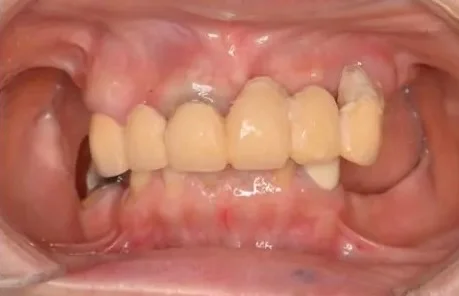

Before

After

上下左右側における歯が多数なくなったところへのインプラント治療(虫歯・歯周病における多数歯欠損)

1年、20回 / 7,700,000円リスク・副作用:多数歯インプラントケースとなり、治療期間の長期化およびインプラント周囲炎のリスク